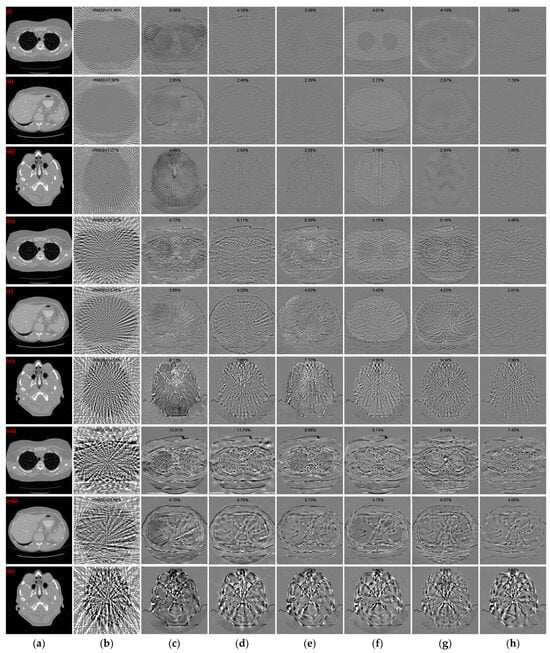

3.2. Qualitative Evaluation

3.4. Robustness of Noise